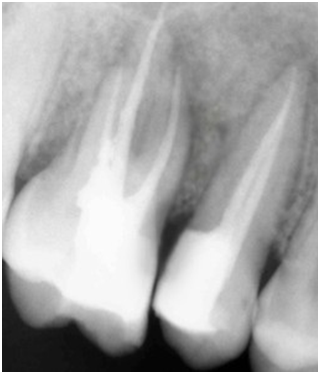

A 22-year old female patient presented in our private dental practice set up with complaint of pain, food stagnation, foul smell and loosening of couple of teeth in upper jaw. Intraoral examination revealed vertical bone loss around distal surface of upper right second premolar and mesial surface of first molar (Figure 1). The pocket depth was measured to be more than 15mm (Figure 2). The severely affected premolar and molar, on pulp testing showed pulpal involvement leading to diagnosis of endo-periodontal lesion.

After 4 weeks, surgical intervention was carried out. Under local anesthesia a full thickness mucoperiosteal flap was reflected to entirely expose the underlying bony defect (Figure 3). Scaling and root planing was again carried out with osteoplasty to make sure the site becomes clean and non-infected. Freeze-dried bone allograft (surreoss) 0.5cc powder was condensed into the bone defect (Figure 4) and 1x2cm Acellular Dermal Matrix Membrane (Surederm) was placed over the graft area to prevent the epithelial cell migration (Figure 5). Finally, interrupted silk (4/0) suture were placed to approximate the soft tissue (Figure 6). Post-operative instructions were given and patient was directed to use chlorhexidine gel and rinse three times for a period of 15 days and suitable antibiotics were prescribed for five days. As the prognosis of tooth was highly questionable patient was recalled on follow up after 1 week, 2 weeks and 4 weeks. After 3-months’ patient’s intraoral radiograph showed remarkable improvement in regard to bone repair and patient’s satisfaction (Figure 7). Clinical evaluation on 3-month, 2-year and 5-year recall exhibited marked reduction in pocket depth up to 12mm with radiographic evidence of further hard tissue repair (Figure 8). A 5-year recall showed a stable probing depth of 3 mm with functionally standing in her oral cavity despite the fact that she refused to have a crown on the treated tooth (Figure 9).

In this case, after careful clinical and radiographic examination, the two adjacent teeth # 15 and 16 were found insensible to thermal tests which led to establish diagnosis of pulp necrosis in the affected teeth. The RCT of the affected teeth was imperative to perform before periodontal correction. Following RCT, the patient’s teeth were meticulously scaled and root-planed to further lower the bacterial load from the periodontal lesion site as RCT followed by NSPT exhibits improvement of clinical parameters long with alveolar bone creation (8).